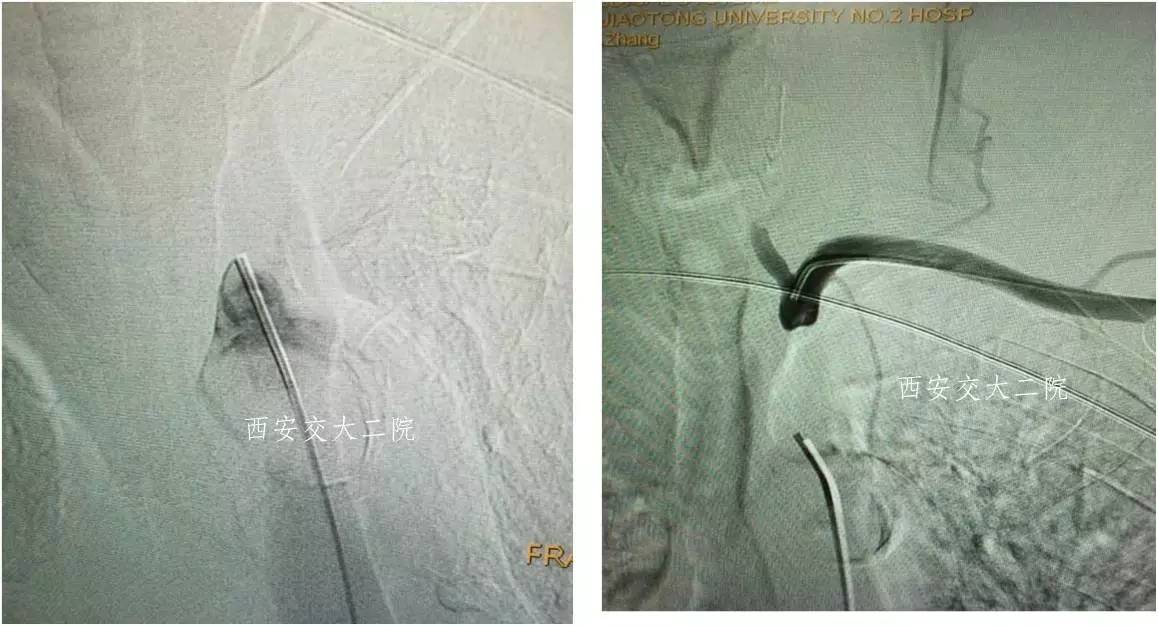

术前DSA

术后DSA